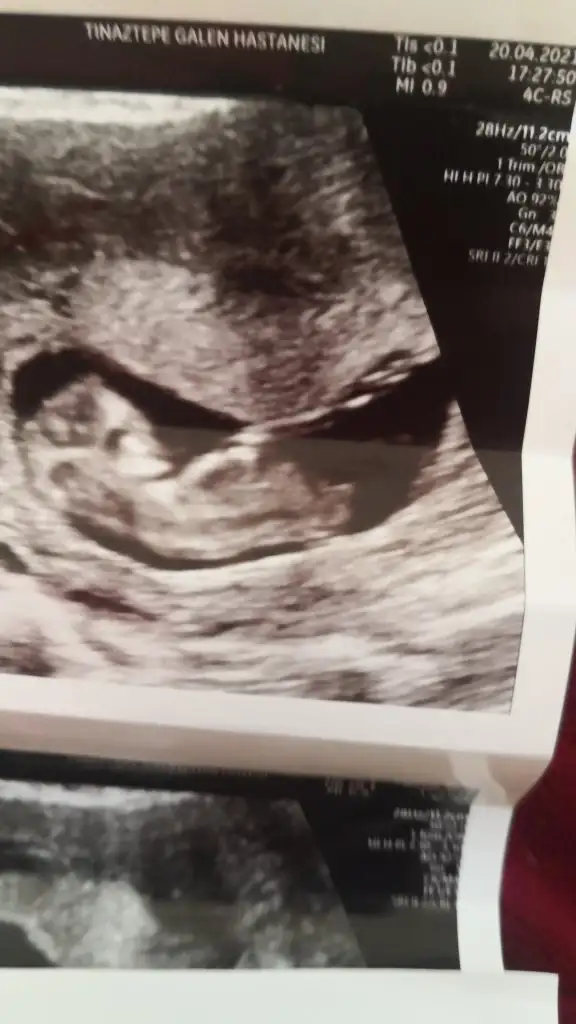

6+4 haftalık bana da yorum yapar mısınız çok merak ediyorum karından görüntüdür.

• 20210324_134131.webp

20210324_134131.webp

16,3 KB · Görüntüleme: 90